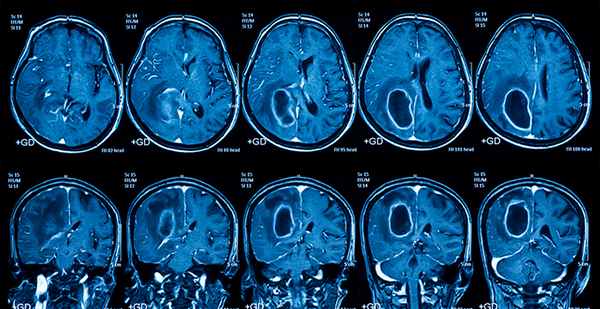

б) Лучевая диагностика ВИЧ-ассоциированного миелита:

• Наиболее распространенный признак: атрофия спинного мозга

• Гиперинтенсивность Т2-сигнала спинного мозга ± неравномерное контрастное усиление:

о Грудной > шейный отдел спинного мозга с краниальным распространением поражения по мере прогрессирования заболевания

(Слева) Сагиттальный срез, МР-И в режиме FLAIR: очаги высокой интенсивности сигнала в толще грудного отдела спинного мозга. Признаков отека спинного мозга нет. Выявленные изменения соответствуют находкам, обнаруживаемым при ВИЧ-ассоцииро-ванном миелите.

(Справа) Аксиальный срез, Т2-ВИ: в правой половине спинного мозга определяется гиперинтенсивный очаг. Признаков отека спинною мозга нет. При контрастировании в Т1 -режиме (здесь не представлено) контрастного усиления сигнала не отмечено. Выявленные изменения соответствуют находкам, обнаруживаемым при ВИЧ-ассоциированном миелите. (Слева) Микрофотограмма, низкое увеличение, окраска Люксолом синим. Видны признаки распространенной губчатой перестройки белою вещества спинного мозга, являющейся проявлением вакуолярной миелопатии. Поражения спинною и головною мозга нередко развиваются отдельно друг от друга, что позволяет предположить различные патогенетические механизмы этих поражений.

• Наиболее распространенной МР-находкой является атрофия спинного мозга, характеризующаяся преимущественным поражением грудного ± шейного отдела спинного мозга